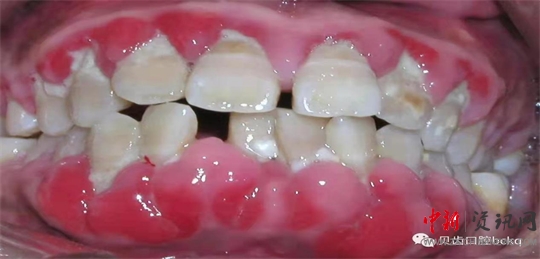

牙周細菌導致的炎癥,只要造成骨頭的流失,我們就叫它牙周炎。牙周炎在中國老百姓當中是比較普遍,大約有80%-90%的發(fā)病率。以往人們對于牙周的重視程度不夠,結果導致后期牙根暴露,牙齒松動,甚至到最后不得不拔掉松動的患牙。

下面這兩張x光片是比較典型的牙周炎的影像資料。該患者的全口所有牙齒都出現了不同程度的松動;颊攥F在感覺無法用牙齒咀嚼。坦白地講,牙周炎發(fā)展到這種程度,很多時候醫(yī)生也束手無策了。為了保留更多的牙槽骨,醫(yī)生回不得不拔掉哪些嚴重松動的患牙。